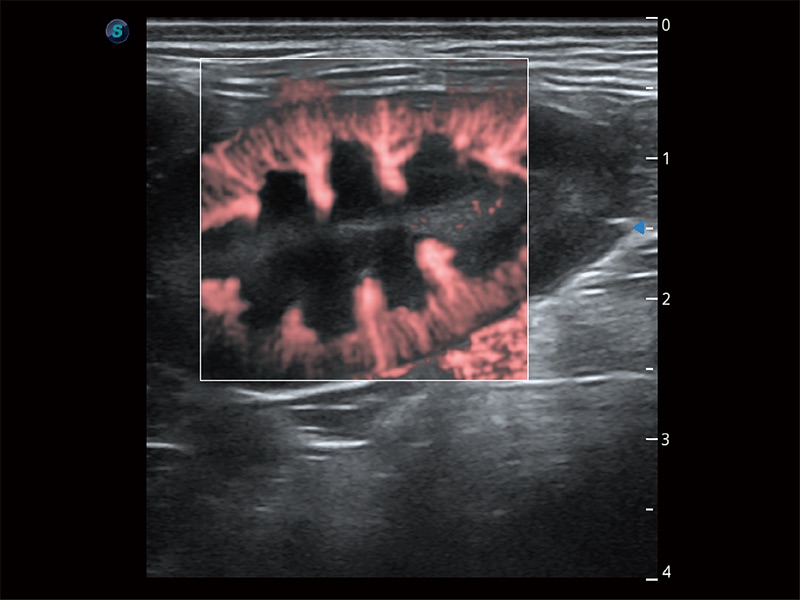

非线性融合造影成像充分利用谐波和基波信号,为难以观察的血流进行增强显像。可用于线阵、凸阵、微凸阵、相控阵探头。